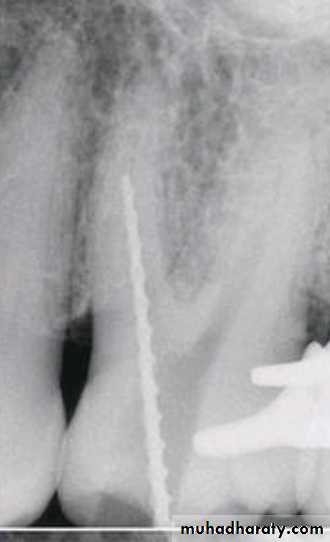

The step-down technique is advocated for cleaning and shaping procedures as it removes coronal interferences and provides coronal taper.

With the pulp chamber filled with irrigant or lubricant, the canal is explored with a small instrument to assess patency and morphology (curvature). The working length can be established at this time.

The coronal one third of the canal is then flared with Gates-Glidden drills or rotary files of greater taper (.06, .08, or .10).

Step-Down Technique

• A large file (such as No. 70) is then placed in the canal, and a watch-winding motion is used until resistance is encountered.

• The process is repeated with sequentially smaller files until the apical portion of the canal is reached. The working length is checked again.

• The apical portion of the canal can now be prepared by enlarging the canal at the corrected working length.